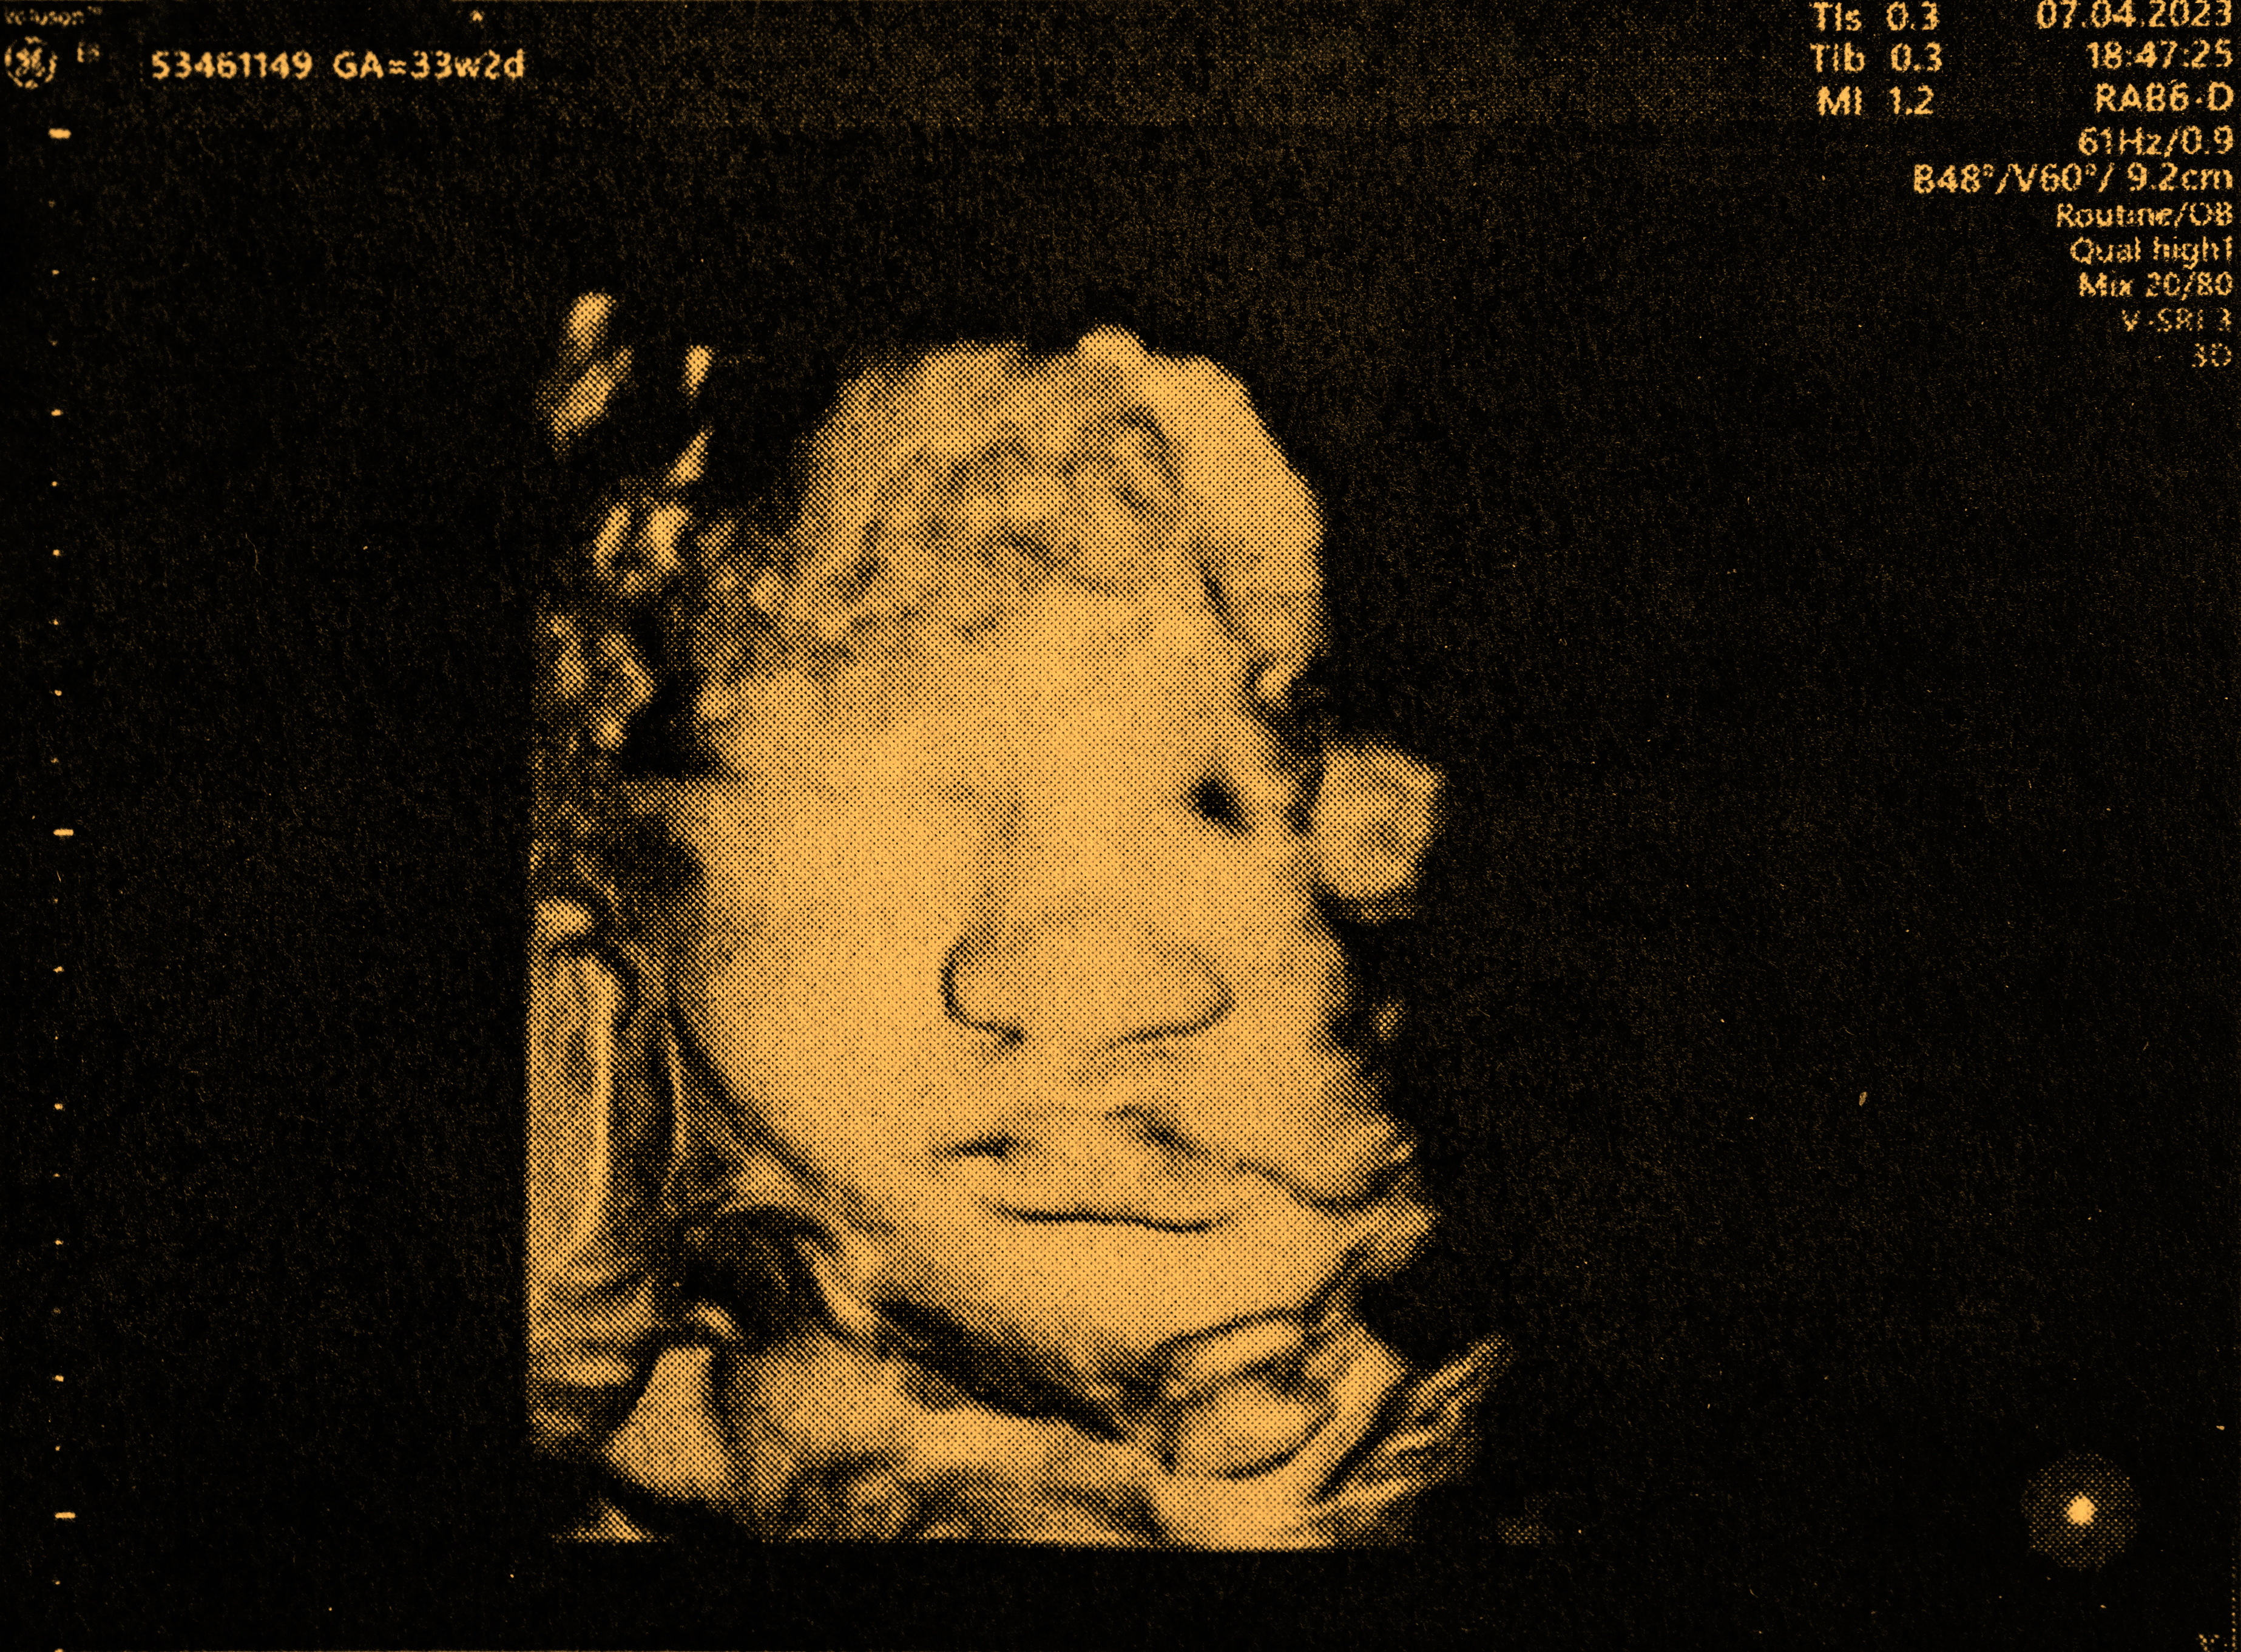

Ein Video, das auf der Plattform X (ehemals Twitter) viral gegangen ist, zeigt die erstaunlichen Aktivitäten von Babys im Mutterleib und hat bereits 21 Millionen Aufrufe gesammelt. Die Aufnahmen dokumentieren, wie Babys im Mutterleib trinken, gähnen, sich dehnen, entspannen, treten, rutschen und sogar springen.

Diese faszinierenden Bilder bieten seltene Einblicke in das Leben vor der Geburt und haben weltweit grosses Interesse ausgelöst. Nutzer auf X sind begeistert von der Vielfalt der Bewegungen, die Babys schon vor ihrer Geburt zeigen.